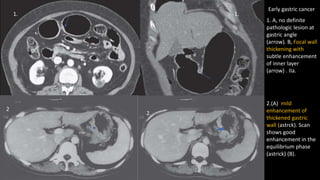

1. A, no definite

pathologic lesion at

gastric angle

(arrow). B, Focal wall

thickening with

subtle enhancement

of inner layer

(arrow) . IIa.

1. 1.

2.(A) mild

enhancement of

thickened gastric

wall (astrck). Scan

shows good

enhancement in the

equilibrium phase

(astrick) (B).

Early gastric cancer

2

.

2.